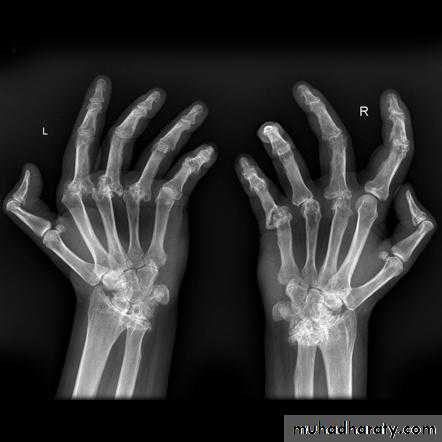

Radiological findings

Radiographic changes typical of RA

The hallmark feature of the disease is persistent symmetric polyarthritis (synovitis) that affects the hands and feet, although any joint lined by a synovial membrane may be involved.Other symptoms:

Usually a polyarthritis with symmetrical joints affected